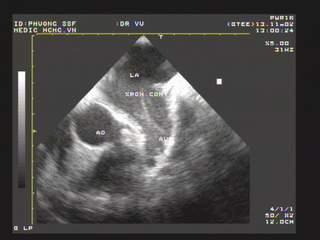

Figure 2. LAX view showing MS with severely calcified mitral leaflets& presence of LA thrombus

Figure 10. 2DTTE parasternal LAX view shows the doming appearance of AML, thickening of subvalvular apparatus, thrombus in LA